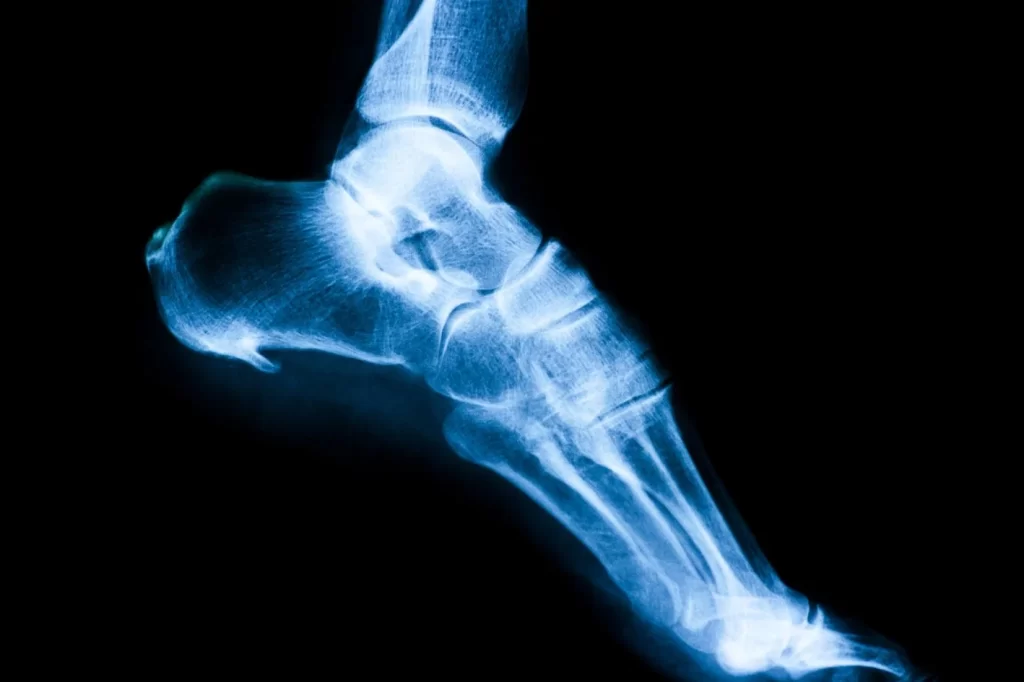

Charcot foot

Charcot foot is a rare condition that arises from uncontrolled diabetes and neuropathy. This usually occurs when an injury (e.g., sprain, fracture) or repeated stress to the foot goes unnoticed due to the lack of sensation caused by peripheral neuropathy. Unfortunately, further walking on the injured foot exacerbates the injury. [3]

Charcot foot is a destructive condition that significantly changes the foot structure. The early symptoms of Charcot foot include swelling, redness, and warmth in the affected foot. As the condition progresses, the bones of the foot start to break, and joints become dislocated and collapse. The foot’s arch also collapses, often resulting in a rounded shape on the bottom of the feet.